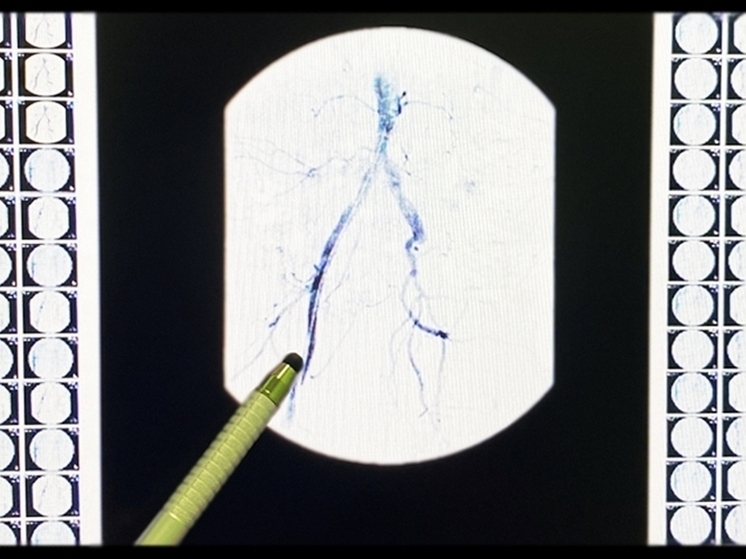

Фото: Рязанская областная клиническая больница

Врачи Рязанской областной клинической больницы провели операцию 51-летнему пациенту с инфарктом миокарда. Об этом сообщили в пресс-службе медучреждения.

В ходе лечения врачи выполнили коронарную ангиографию для оценки состояния сосудов, так как ситуация осложнялась увеличенным диаметром артерии.